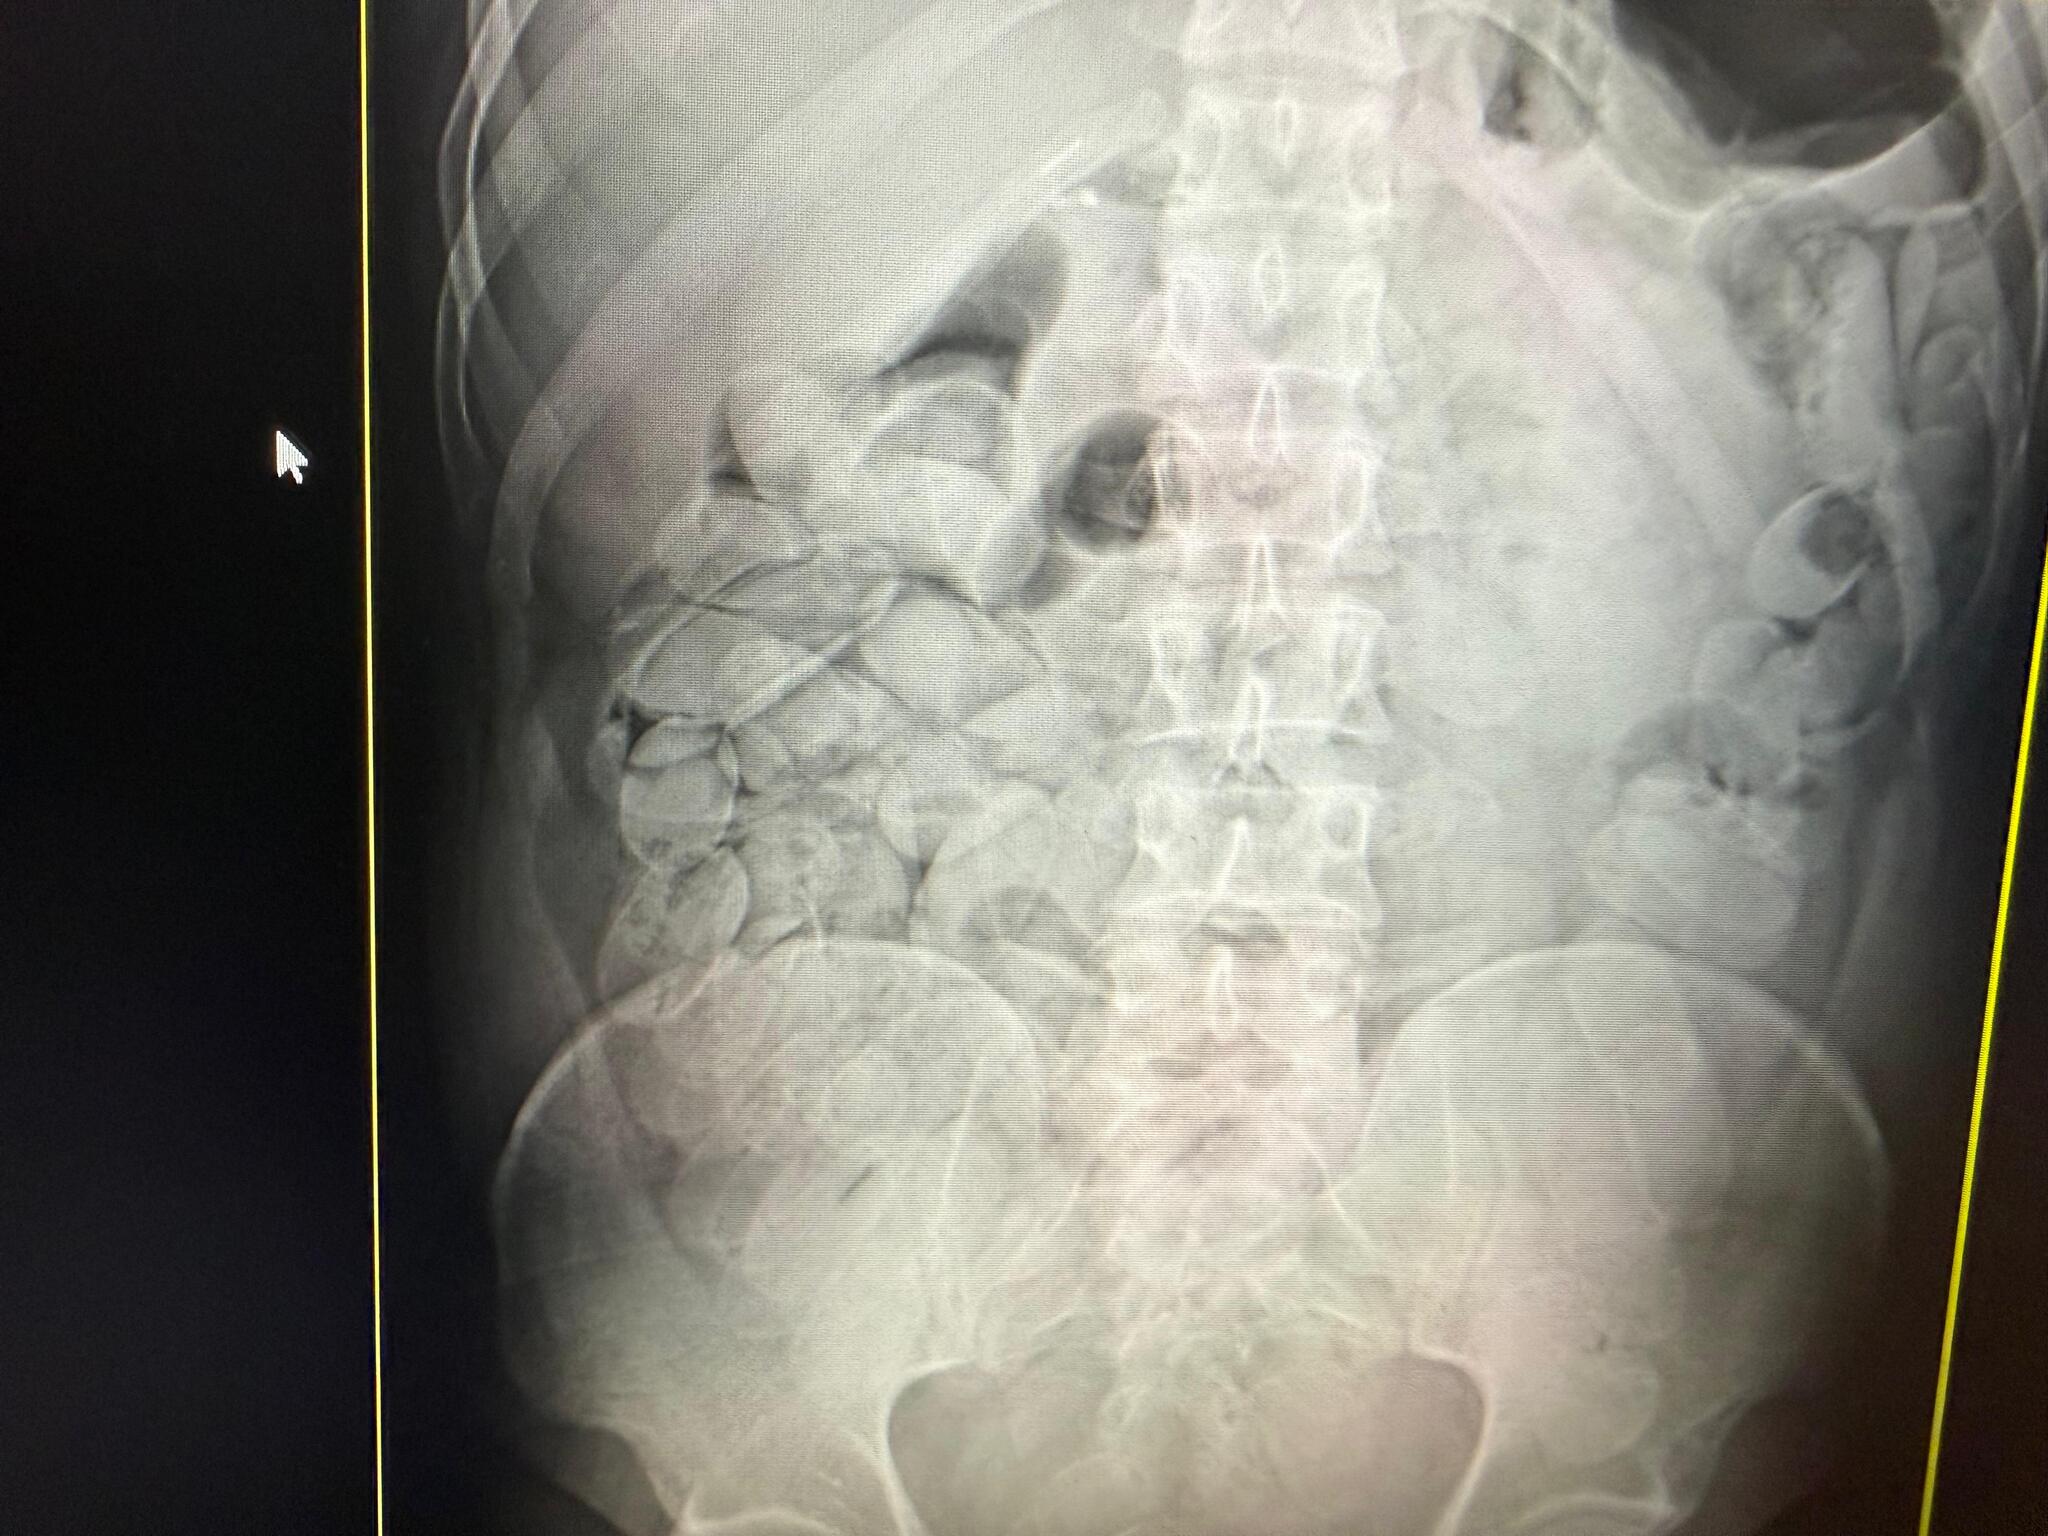

Um inspetor da Receita Federal informou que um dos presos não conseguiu engolir as cápsulas, que foram encontradas em sua mochila. Os demais detidos foram encaminhados ao pronto-socorro, onde exames de raio X constataram que haviam ingerido cápsulas de cocaína.